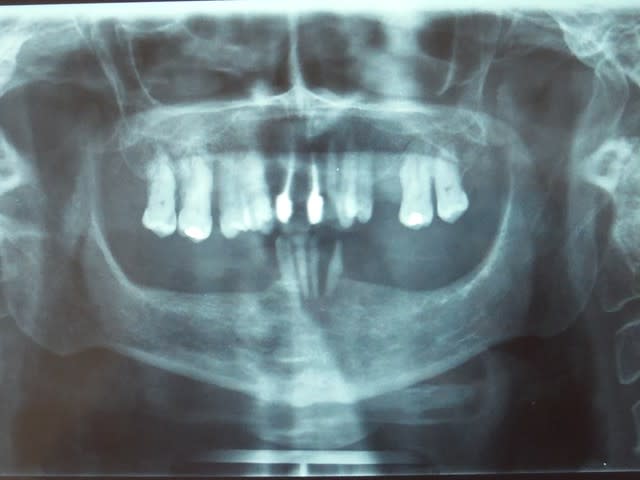

Il manquait la pano, pas de douleur au niveau de l'émergence du dentaire inférieur, comme quoi...

L'autre pano c'est un cas top de chez top, effondrement de la DV en "occlusion" la patiente touche la crête édentée avec ses M et PM, je vais faire une immédiate (un suicide thérapeutique!) partielle pour le maxillaire, et complète (of course) pour la mandibule.